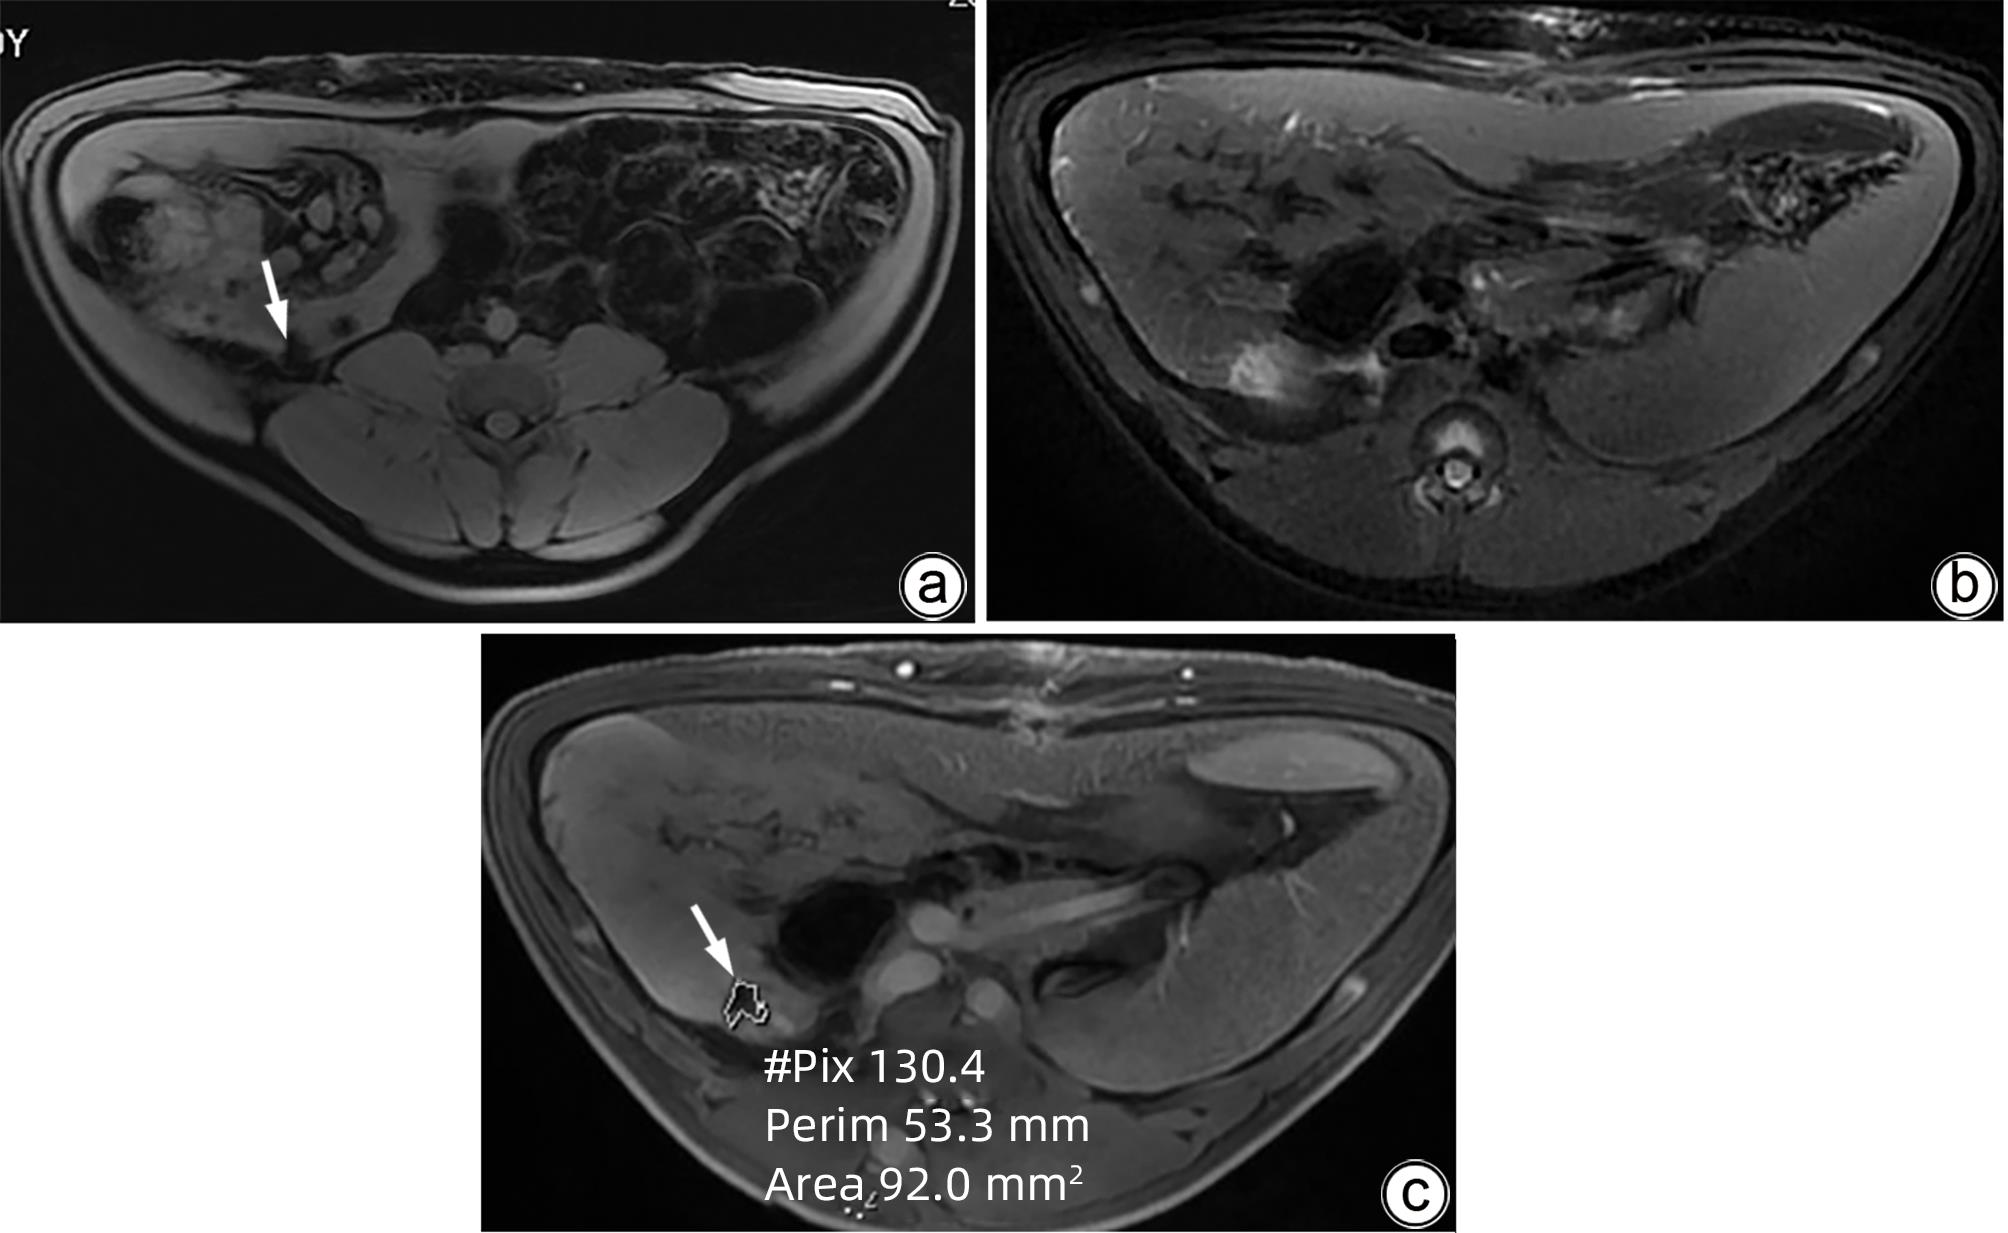

磁共振质子密度脂肪分数(MRI-PDFF)评估慢性HBV感染者肝脂肪变性及分布特点

王丽旻, 包超, 赵凯越, 靳婕华, 郑卓肇, 黄缘

2024, 40(5): 934-939. DOI: 10.12449/JCH240511

摘要(1716) HTML (520) PDF (616KB)(95)

摘要:

目的  利用磁共振质子密度脂肪分数(MRI-PDFF)评估慢性HBV感染者的肝脂肪变性的程度。  方法  选择北京清华长庚医院2018年1月—2022年12月门诊或者住院,明确诊断为慢性HBV感染,年龄>16岁的患者。所有患者均在本院行肝脏磁共振检查。依据是否合并肝硬化进行分组,比较患者的各个肝段PDFF值的一致性。使用Kappa一致性检验、组内相关系数(ICC)进行一致性分析。  结果  纳入76例核苷(酸)类似物经治患者,其中30.26%(23例)合并肝硬化,所有患者的MRI-PDFF算术均值波动在1.49%~30.93%,依据MRI-PDFF≥5%诊断为脂肪肝,38.16%(29例)患者合并脂肪肝。76例患者的全肝PDFF算术均值低于全肝PDFF加权均值,全肝PDFF加权均值、全肝PDFF算术均值、左半肝及右半肝的PDFF算术均值比较,差异无统计学意义(F=0.39,P=0.76)。各个肝段、左/右半肝PDFF算术均值与全肝PDFF加权均值、全肝PDFF算术均值的一致性较强(ICC均>0.75),但右半肝PDFF算术均值与全肝PDFF加权均值的一致性高于左半肝。合并肝硬化组患者在区分脂肪肝诊断的一致性检验方面,Ⅶ段PDFF算术均值与全肝PDFF加权均值一致性差(Kappa=0.39),左半肝、Ⅰ、Ⅱ、Ⅲ、Ⅴ、Ⅵ、Ⅷ为中等一致。合并肝硬化的患者Ⅶ段PDFF算术均值与全肝PDFF加权均值一致性最低,Ⅳ段一致性最高。未合并肝硬化的患者Ⅱ段PDFF算术均值与全肝PDFF加权均值一致性最低,Ⅴ段的一致性最高。  结论  MRI-PDFF评估慢性HBV感染者的肝脂肪变性更全面,合并肝硬化的患者各肝段PDFF算术均值与全肝PDFF加权均值的一致性差异大。